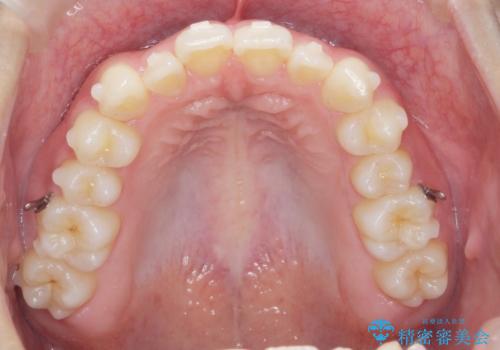

マウスピース矯正で前歯のガタつきを改善

- 上下の前歯のガタつきの改善を求めて、矯正治療を希望され来院されました。

矯正検査の結果、マウスピース矯正システム インビザラインの適応であることからワイヤーを用いず矯正治療を進めることとしました。

1日20時間以上の使用時間をきっちりと守っていただけたため、良好な治療結果、歯並びを手に入れることができました。